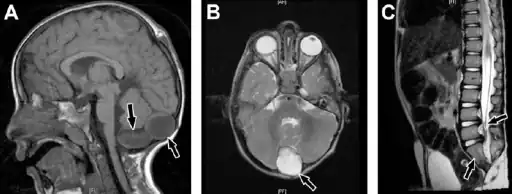

In terms of the diagnosis of Caudal regression syndrome we find that the following is used:[6]